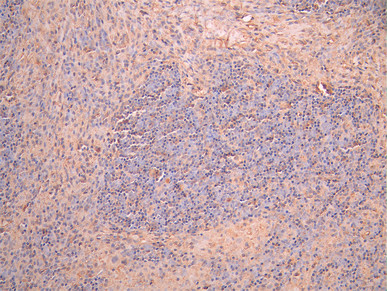

IHC image of CSB-RA006255MA1HU diluted at 1:50 and staining in paraffin-embedded human lymph node tissue performed on a Leica BondTM system. After dewaxing and hydration, antigen retrieval was mediated by high pressure in a citrate buffer (pH 6.0). Section was blocked with 10% normal goat serum 30min at RT. Then primary antibody (1% BSA) was incubated at 4°C overnight. The primary is detected by a Anti-Human lgG, Fcy Fragment Specific labeled by HRP and visualized using 0.05% DAB.